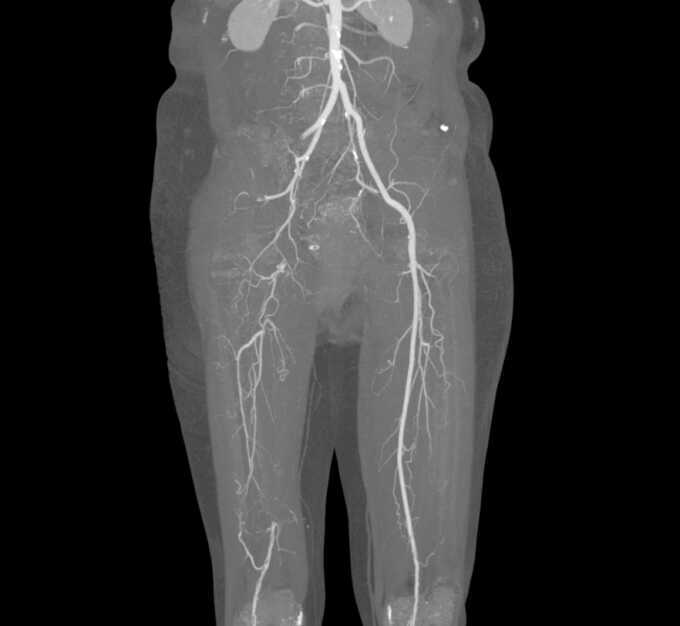

ThS.BS.CKI Phạm Ngọc Minh Thủy, chuyên khoa Ngoại Tim mạch, Phòng khám Đa khoa Tâm Anh Quận 7, chẩn đoán bà Kiệu bị huyết khối cấp trên nền bệnh mạch máu mạn tính (hẹp do xơ vữa). Cục máu đông lấp hoàn toàn lòng động mạch, kéo dài từ động mạch chậu ngoài bên phải đến toàn bộ động mạch đùi phải và các mạch máu bên dưới. Tình trạng này làm cho chân phải bị thiếu máu nghiêm trọng, có nguy cơ hoại tử chi nếu không điều trị.

Do huyết khối lan rộng và mức độ vôi hóa phức tạp, êkíp Ngoại Tim mạch, Bệnh viện Đa khoa Tâm Anh TP HCM, quyết định phẫu thuật tái tưới máu cho chân phải bệnh nhân. Sau khi đánh giá các yếu tố nguy cơ tim mạch, điều chỉnh thuốc gây chảy máu, bệnh nhân được phẫu thuật lấy toàn bộ huyết khối động mạch chậu đùi, động mạch ở cẳng chân đồng thời tạo hình mở rộng vị trí động mạch bị hẹp nặng ở động mạch đùi và khoeo.

Theo ThS.BS Trần Thúc Khang, Phó khoa Ngoại Tim mạch, Trung tâm Tim mạch, để đánh giá kết quả tái thông động mạch đạt yêu cầu hay không (không hẹp tồn lưu, mạch máu bên dưới thông tốt), phẫu thuật viên sử dụng màn tăng sáng chụp kiểm tra ngay trên bàn mổ.